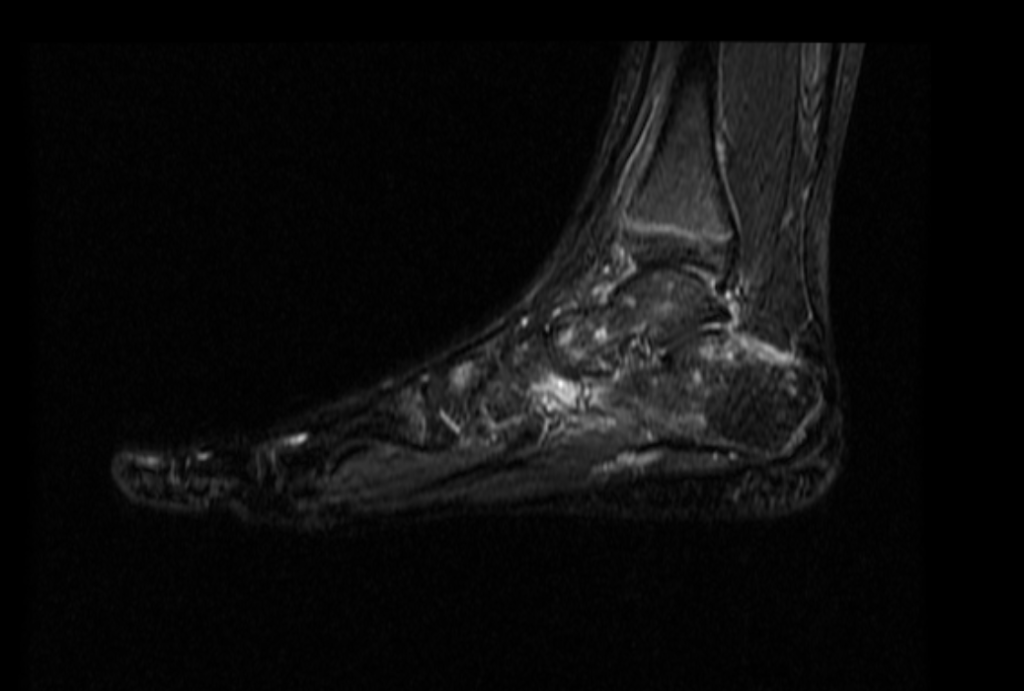

Uzupełniające badanie rezonansu magnetycznego (MR) wykazało:

• obrzęk szpiku kostnego,

• reakcję przeciążeniową,

• obniżenie łuku podłużnego przyśrodkowego.

Połączenie USG i MR pozwala na pełną ocenę anatomiczną i funkcjonalną stopy, co ma kluczowe znaczenie dla dalszego leczenia.